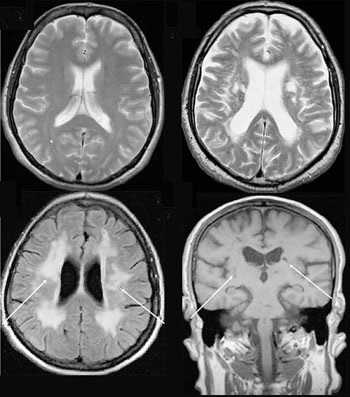

4. МРТ при повреждении Беннетта:

• PD/промежуточная FS:

о Низкоинтенсивный сигнал оссификации от задненижнего края суставной впадины:

- Может смешиваться с низким сигналом капсулы

о Окружающий неоднородный сигнал фиброза и утолщенной капсулы

о Острая травма: высокий сигнал отека вокруг оссификации

о ± Линейный высокий сигнал в разрыве задней губы:

- Сопровождает повреждение Беннетта

- Разрыв задневерхней губы при внутреннем импиджменте

(Справа) На осевой МР-артрограмме Т1ВИ и МРТ Т1ВИ FS у этого же пациента определяется неоднородный сигнал, соответствующий участку оссификации. Участок высокоинтенсивного сигнала на томограмме без жироподавления может соответствовать желтому костному мозгу. Более того, у пациента имеется внутренний импиджмент с разрывами губы и манжеты и поэтому, предполагалось, что повреждение Беннетта не вызывало болевой синдром.